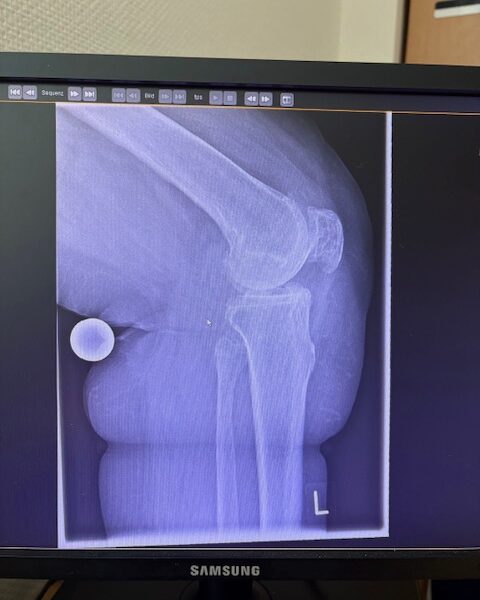

Η 80χρονη ασθενής παρουσίαζε έντονο πόνο και δυσκαμψία στο αριστερό γόνατο τα τελευταία χρόνια. Ο πόνος είχε επιδεινωθεί, επηρεάζοντας τη βάδιση και τη συνολική κινητικότητα, ενώ δυσκολευόταν ακόμα και σε απλές δραστηριότητες όπως το ανέβασμα σκαλοπατιών ή το περπάτημα σε μικρές αποστάσεις. Με την υπάρχουσα πρόθεση ισχίου στην αριστερή πλευρά η ασθενής ήταν αρκετά ευχαριστημένη. Ο ακτινολογικός και κλινικός έλεγχος ανέδειξε προχωρημένη οστεοαρθρίτιδα του αριστερού γόνατος, με πλήρη απώλεια του αρθρικού χόνδρου και παραμόρφωση του μηροκνημιαίου άξονα. Μετά από ανάλυση όλων των επιλογών, αποφασίστηκε η Ολική Αρθροπλαστική Γόνατος με Ρομποτική Υποβοήθηση, με στόχο την απόλυτη ακρίβεια στην τοποθέτηση των εμφυτευμάτων και την αποκατάσταση της φυσιολογικής μηχανικής του γόνατος.